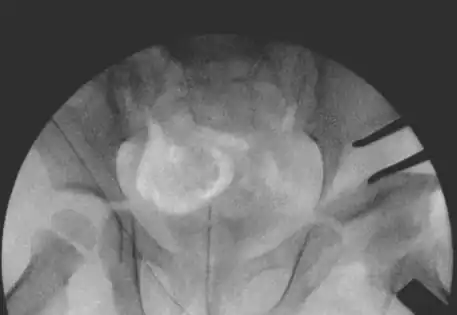

- Arthrogram: A special dye is injected into the hip joint to help the surgeon see any blockages and check how well the hip socket can hold the ball of the joint.

- Arthrogram (dye study) to outline the anatomy of the joint and determine whether a closed reduction is feasible.